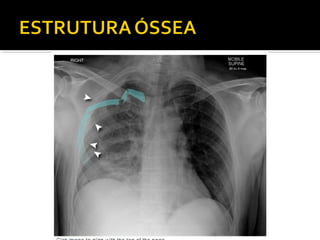

Este documento fornece parâmetros técnicos para realizar uma radiografia de tórax, incluindo posicionamento correto do paciente, dose adequada de radiação e estruturas anatômicas a serem avaliadas, como coração, pulmões, pleura, diafragma e ossos do tórax.